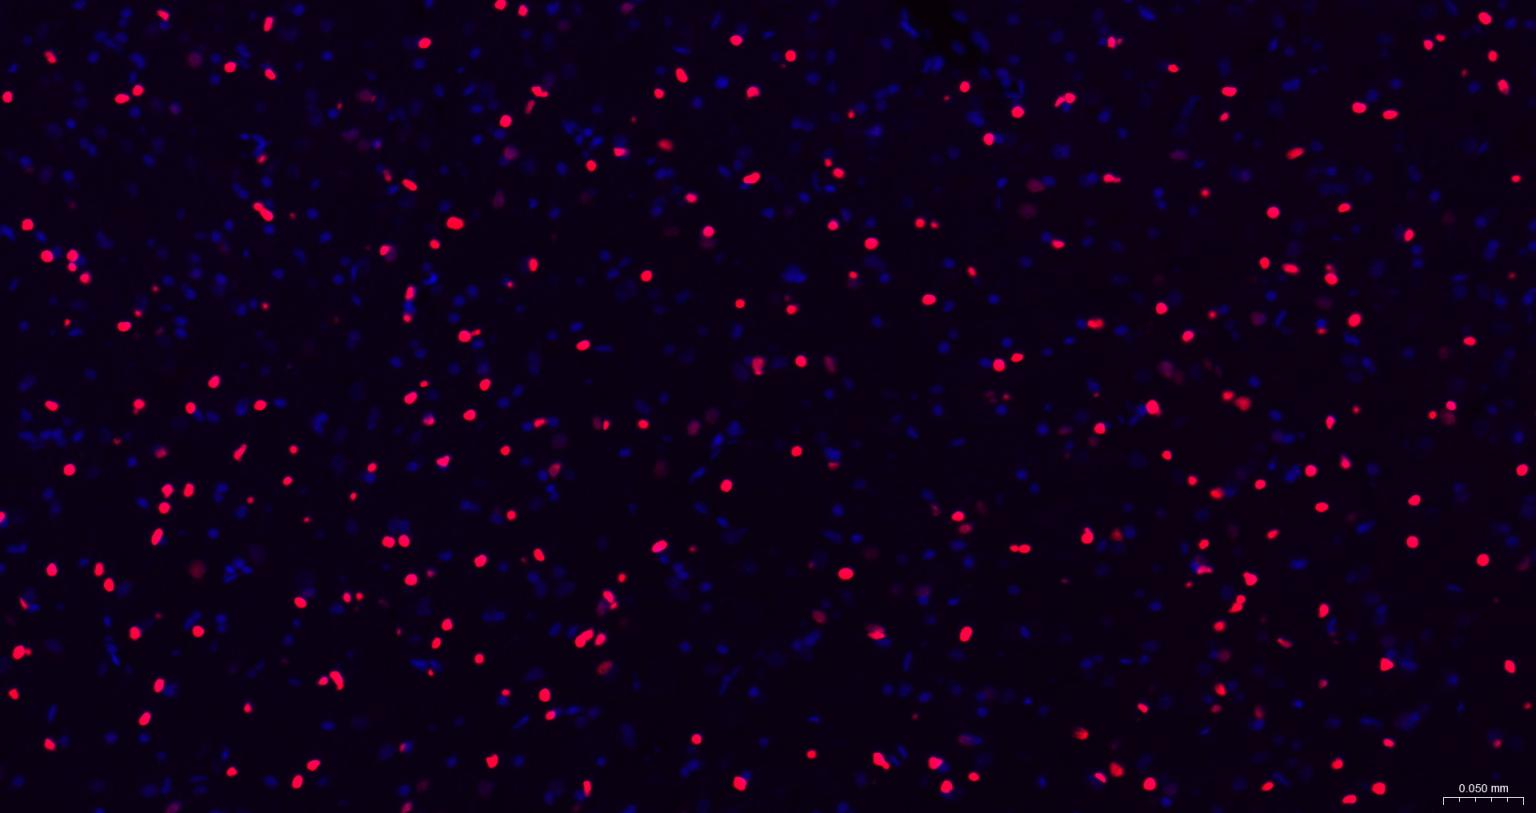

Paraformaldehyde-fixed, paraffin embedded Human Cerebrum; Antigen retrieval by boiling in sodium citrate buffer (pH6.0) for 15 min; The section was incubated with SOX2 Monoclonal Antibody, Unconjugated (bsm-60788R) at 1:200 overnight at 4°C. Followed by conjugated Goat Anti-Rabbit IgG antibody (Red, bs-0295G-BF594), DAPI (blue, C02-04002) was used to stain the cell nuclei.

Paraformaldehyde-fixed, paraffin embedded Mouse Cerebrum; Antigen retrieval by boiling in sodium citrate buffer (pH6.0) for 15 min; The section was incubated with SOX2 Monoclonal Antibody, Unconjugated (bsm-60788R) at 1:200 overnight at 4°C. Followed by conjugated Goat Anti-Rabbit IgG antibody (Red, bs-0295G-BF594), DAPI (blue, C02-04002) was used to stain the cell nuclei.

Paraformaldehyde-fixed, paraffin embedded Rat Cerebrum; Antigen retrieval by boiling in sodium citrate buffer (pH6.0) for 15 min; The section was incubated with SOX2 Monoclonal Antibody, Unconjugated (bsm-60788R) at 1:200 overnight at 4°C. Followed by conjugated Goat Anti-Rabbit IgG antibody (Red, bs-0295G-BF594), DAPI (blue, C02-04002) was used to stain the cell nuclei.